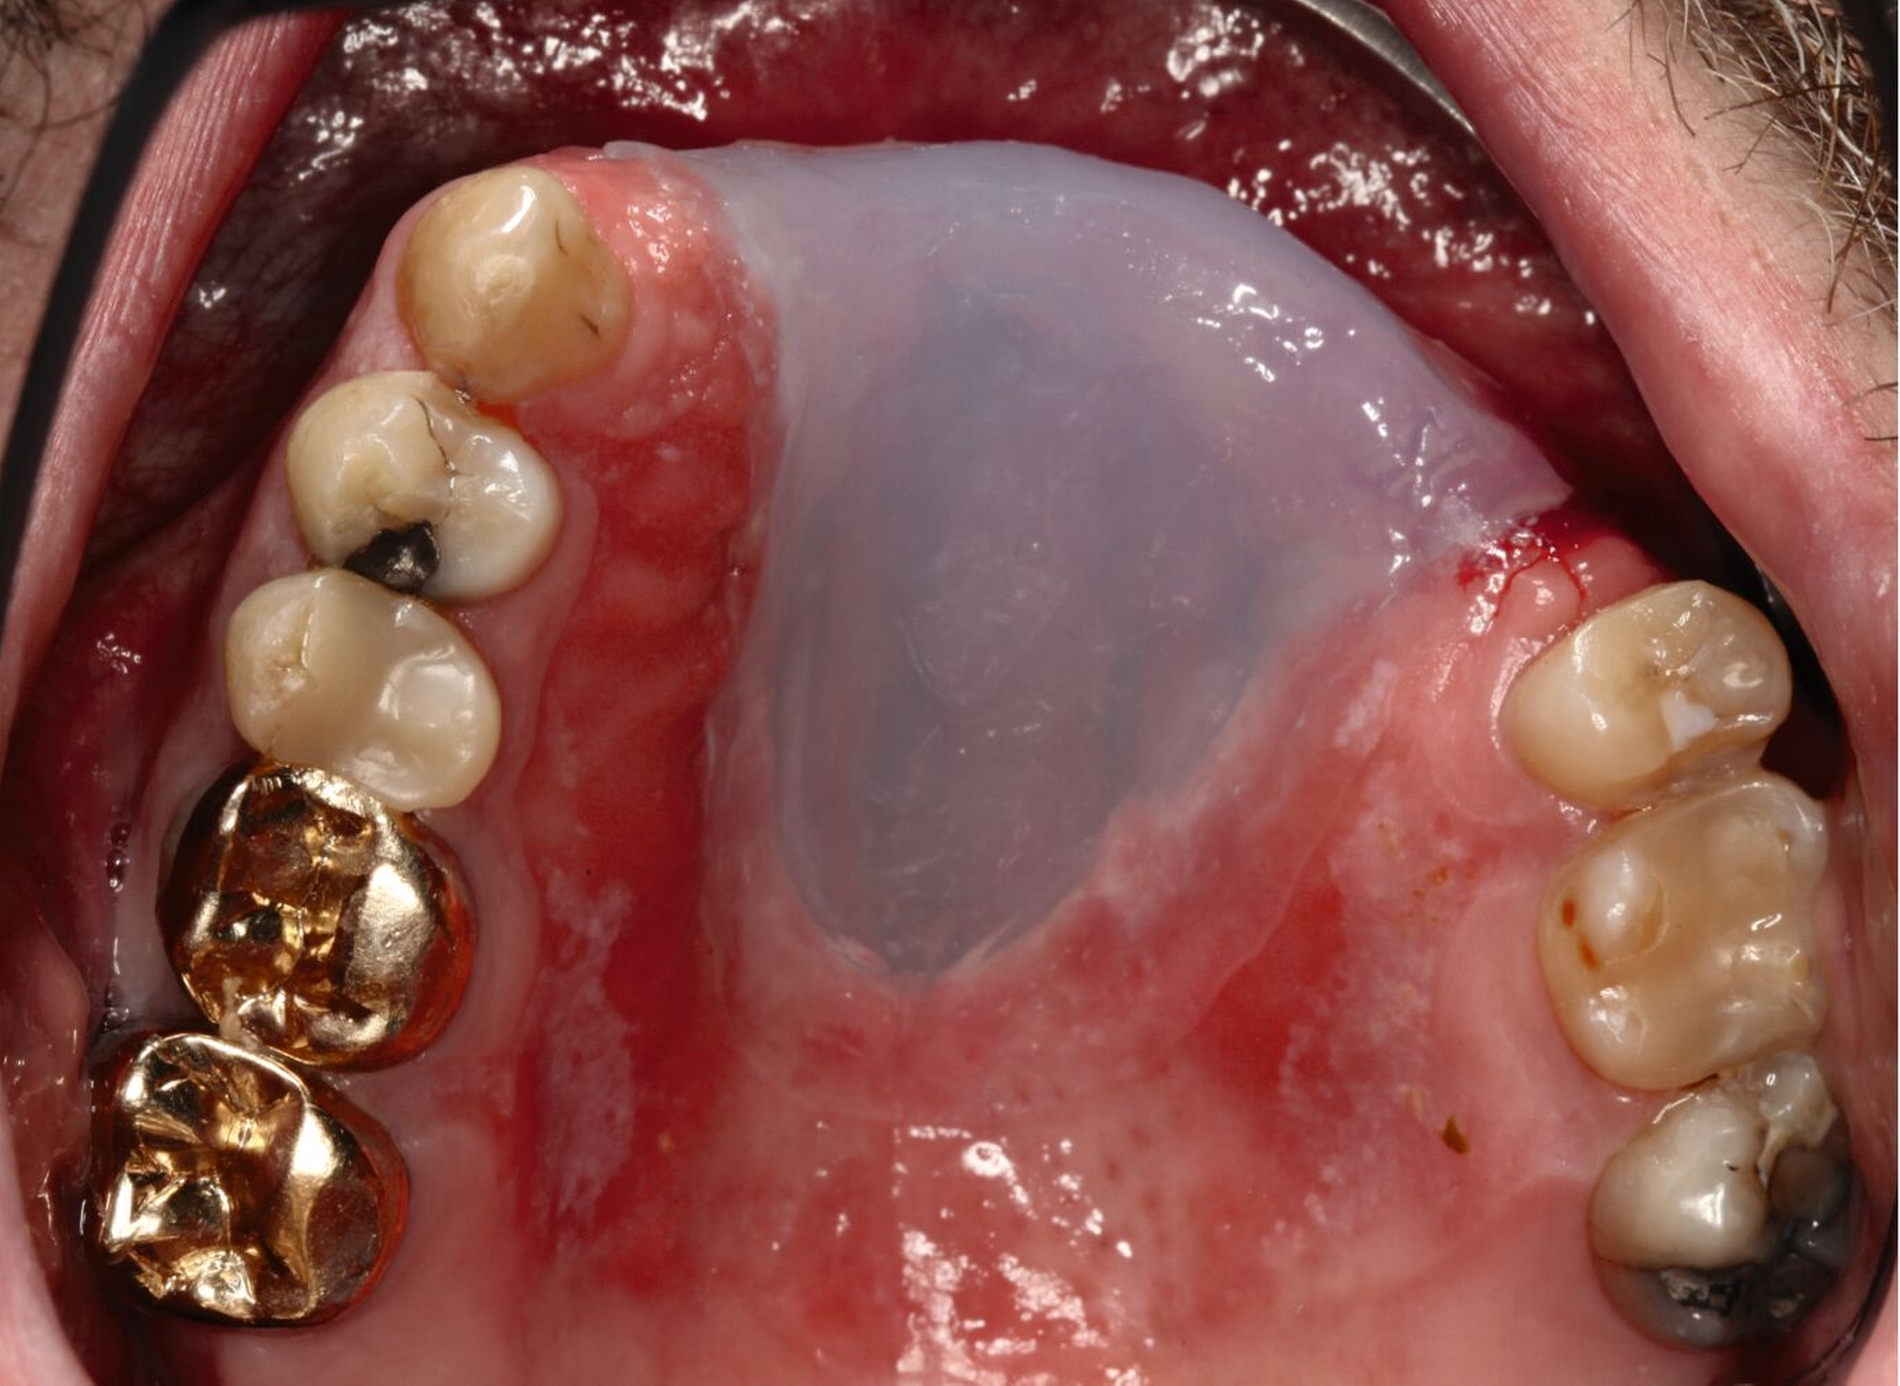

Mit Einbringen eines Wendel-Tubus zur Sicherung der Atemwege, lässt sich der Defekt ohne Probleme abformen (Abbildung 3). Jener verhindert auch, dass der spätere Silikon-Obturator die Atemwege nicht verlegt. Speziell visköses Silikon-Abformmaterial („Laborsilikon Orange“, 12 Shore A, Institut für Anaplastologie Schilling, Würzburg, Deutschland) verhindert ebenfalls, dass die Abformmasse in Richtung des Pharynx fließt. Nach der Defektabformung können die herkömmlichen Arbeitsschritte für einen Zahnersatz (als Zusatz zum Silikon-Obturator oder zur Herstellung einer Obturator-Prothese) erfolgen.